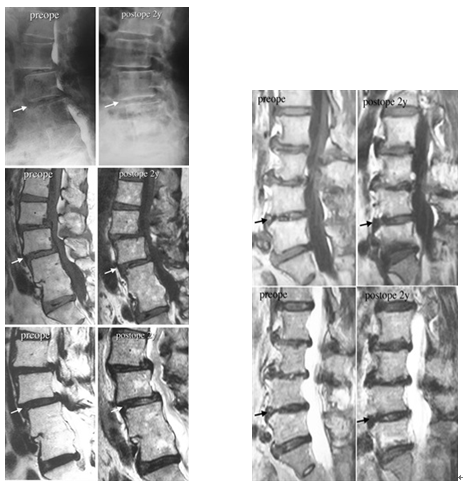

再以椎间盘退化为例。一篇案例报道显示:两例腰椎间盘明显退化的患者接受了含有间充质干细胞的胶原海绵片治疗,2年后,CT和MRI显示两名患者的退化椎间盘得到修复,椎间真空现象有所改善,在T2加权MRI上,与治疗前相比,椎间盘的信号强度增高,表明水分含量增高。手术后症状也得到缓解,腰背痛,小腿麻木,疼痛等症状显著减轻。